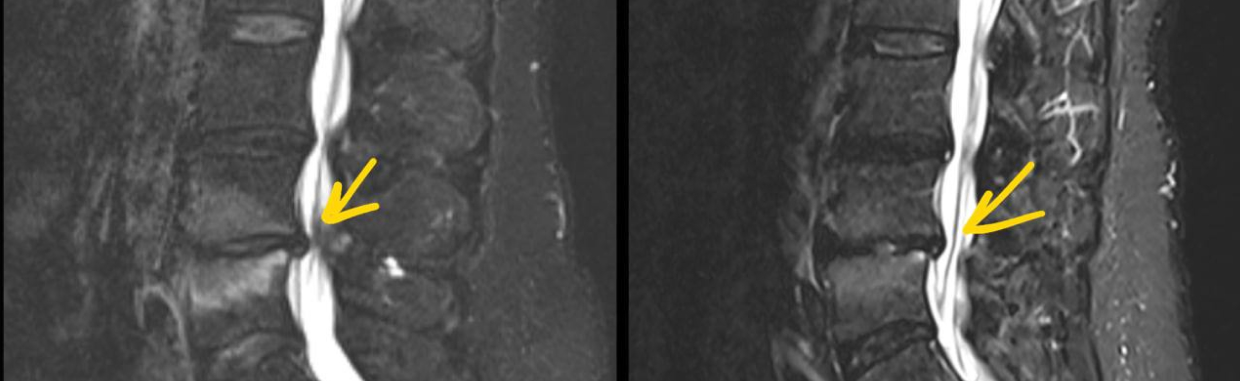

До лечения

Пациент 40 лет.

— На МРТ поясничного отдела позвоночника определяется стеноз позвоночного канала, связанный с гипертрофией и отеком желтой связки, что приводит к сужению просвета канала и давлению на дуральный мешок.

— В области желтой связки визуализируется участок повышенного сигнала, соответствующий воспалительному отеку мягких тканей.

— Клинически состояние сопровождалось слабостью в ногах и ограничением дистанции ходьбы, характерными для нейрогенной перемежающейся хромоты при стенозе позвоночного канала.

После лечения

После курса консервативной терапии отмечается положительная динамика: на контрольном МРТ определяется уменьшение отека и толщины желтой связки, что приводит к расширению просвета позвоночного канала и снижению компрессии дурального мешка. Это сопровождается улучшением клинического состояния пациента — уменьшением слабости в ногах и увеличением дистанции безболевой ходьбы.